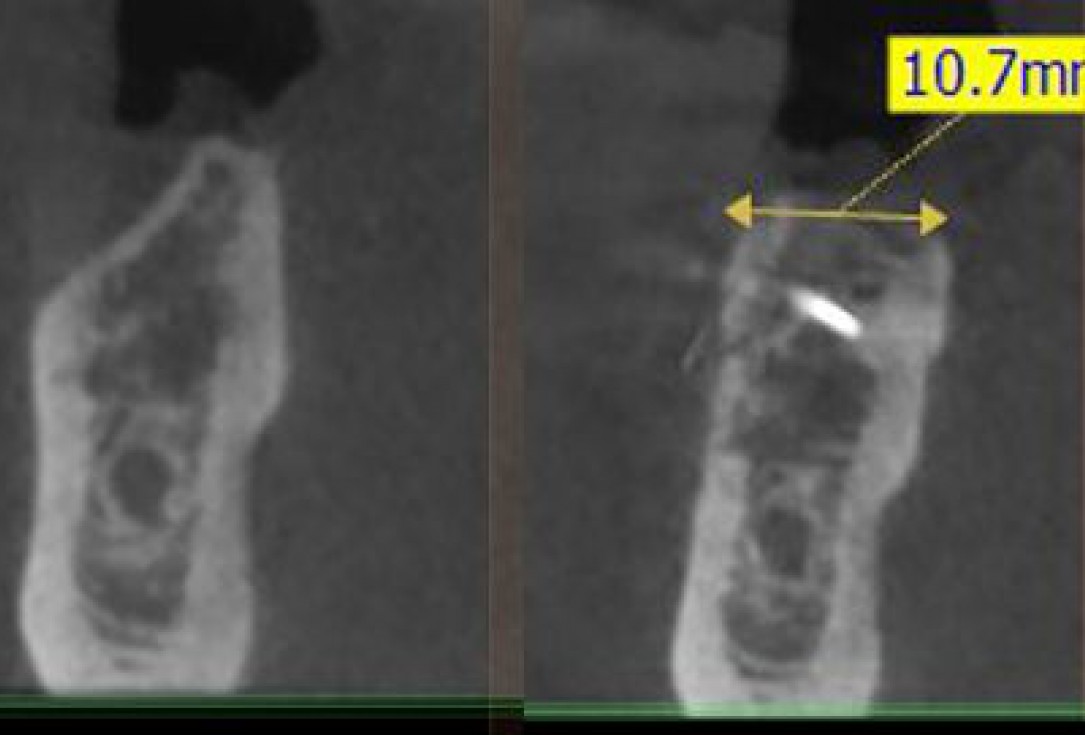

14/28 - Sagittal section of the alveolar ridge in the region of the defect before the augmentation and after 5 months of healing at implantationThree-dimensional augmentation with maxgraft® cortico - Dr. R. Würdinger